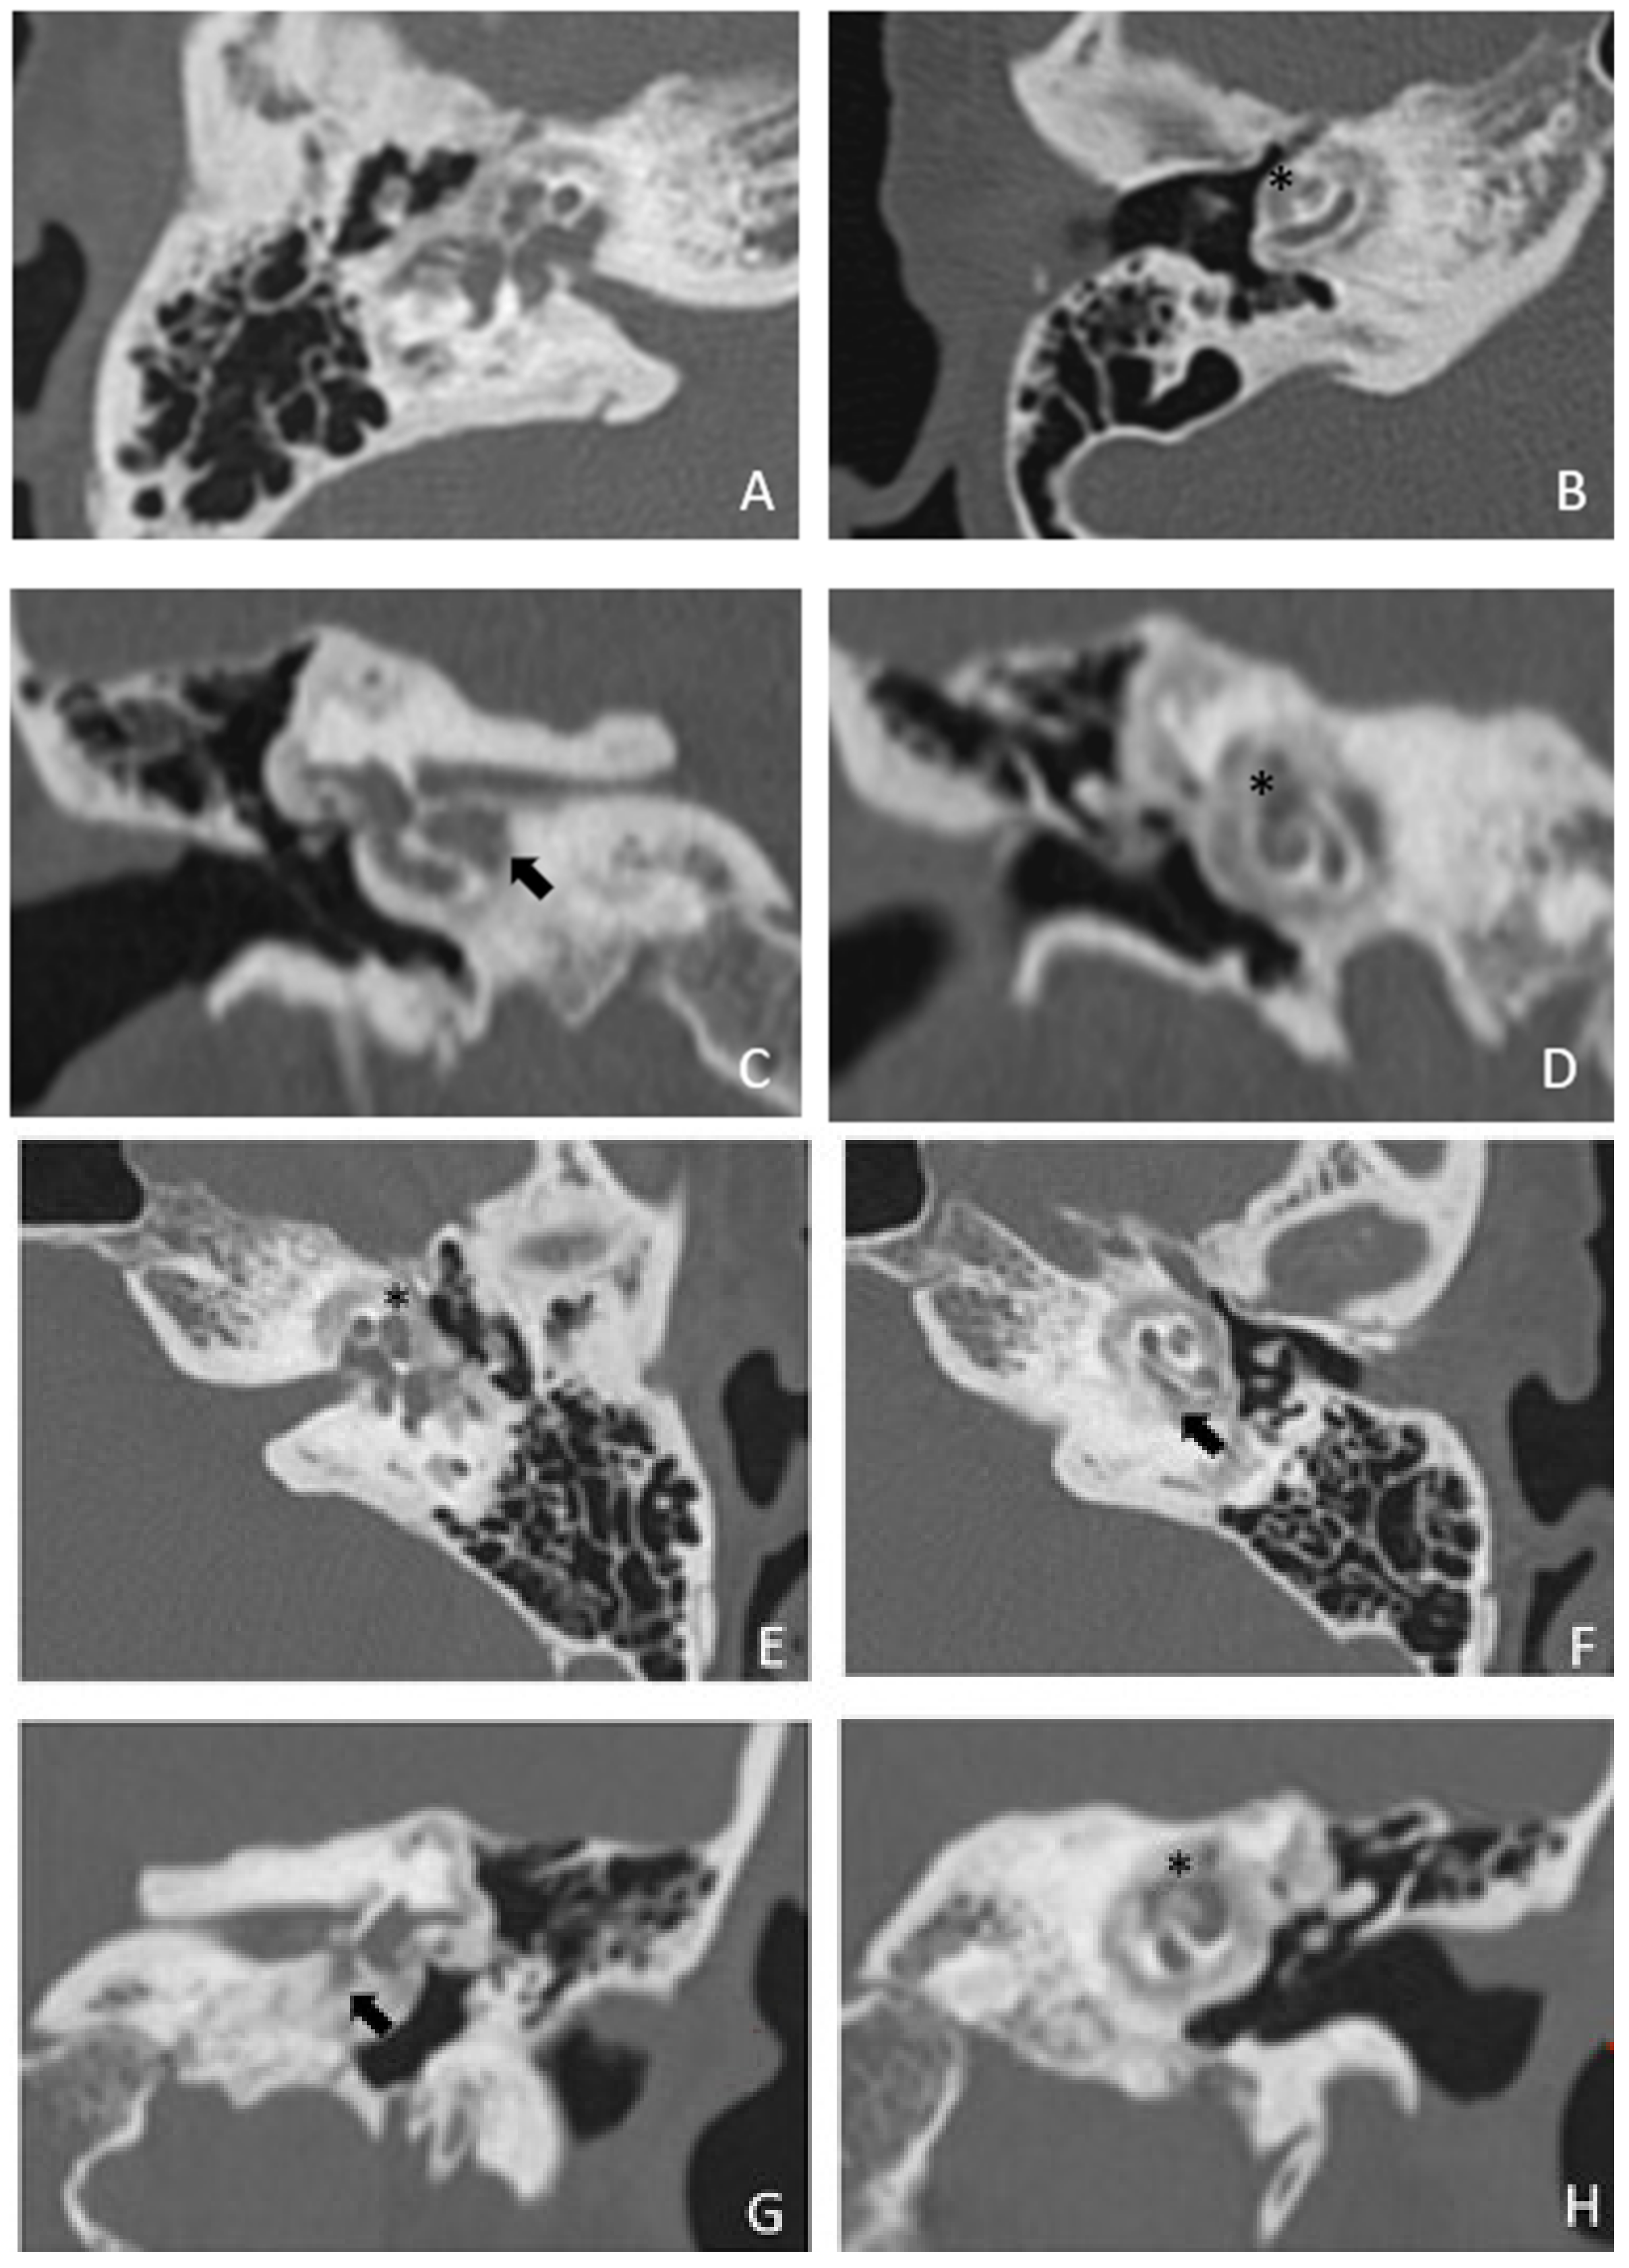

Figure 1.

CT images of patient #1 with osteogenesis Imperfecta. (A,B), right side in axial plane. (C,D), right side in coronal plane. (E,F), left side in axial plane. (G,H), left side in coronal plane. A pericochlear cavity is visible in all figures; arrows indicate its origin from the IAC. Asterisks indicate extension of osteorarefation into the cochlea.

Within a few years, both ears showed a worsening of bone threshold to SNHL bilaterally. In 2017 (27 years since diagnosis) she developed profound SNHL with left-sided anacusis and underwent cochlear implantation in the left ear. CT and MR images showed a large cavity around the basal turn of the cochlea and massive osteorarefaction around the cochlea (‘double ring’ sign). The cavity appeared to contain cerebrospinal fluid but did not communicate with the cochlear lumen (Figure 1 and Figure 2).